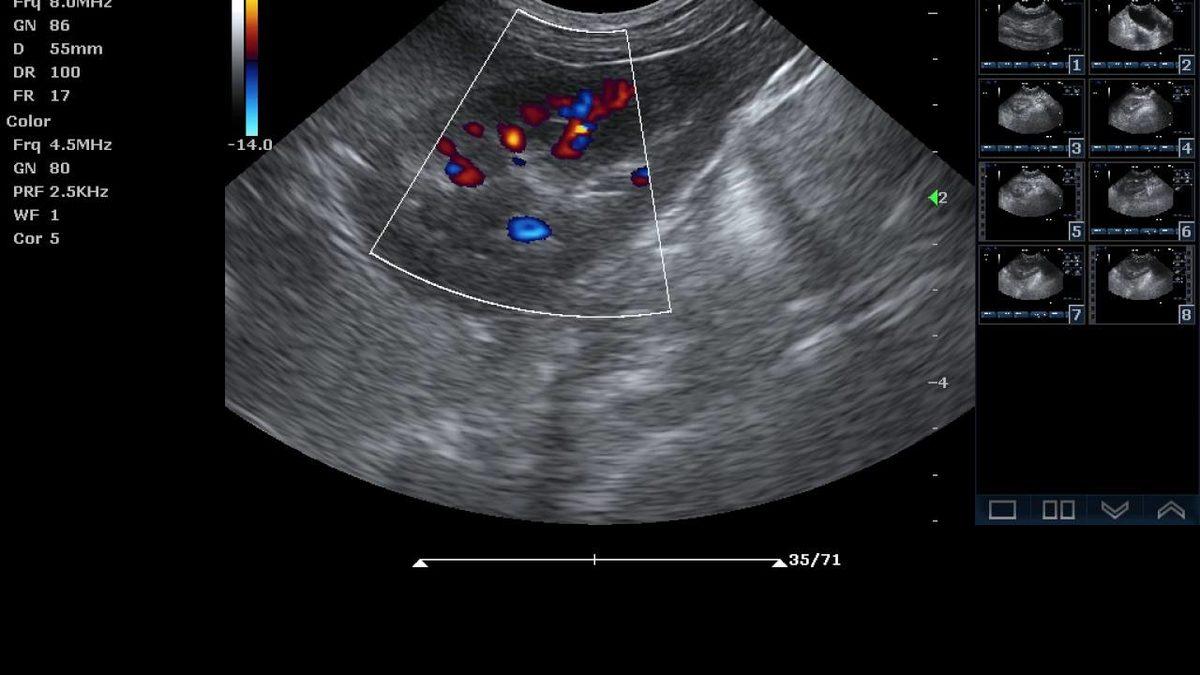

Renkli ultrason:

Renkli ya da diğer adıyla doppler ultrason, genel olarak riskli bir gebelik geçiren anne adaylarına ya da kan dolaşımı ile ilgili şüphe duyulan hastalara uygulanır. Renkli ultrason, kan akışını ve plasentayı kontrol eder. Görüntüdeki renkler gerçeği yansıtmaz. Görünen renkler kan akışının proba yaklaşması ve uzaklaşması ile değişmektedir. Zorunlu bir işlem değildir, doktorlar tarafından riskli bir durumdan şüphelenildiği zaman özel olarak istenir.